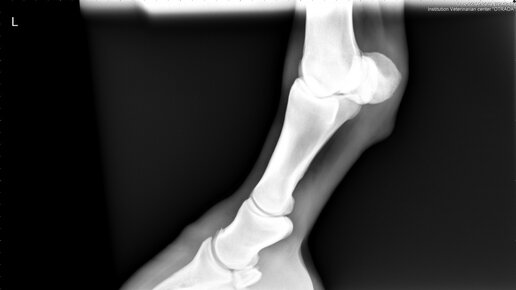

Рентген лошади

11.04.2016 Цена рентгена лошади в Москве - 8000 рублей выезд + 1000 рублей каждый дополнительный снимок.

У лошадей в большинстве случаев основанием для назначения рентгенологического обследования является хромота или травма конечности, но также не редки ситуации, требующие диагностики в области головы (патологии пазух, зубов, височно-нижнечелюстного сустава) или позвоночника (шейного, грудного или поясничного отделов).